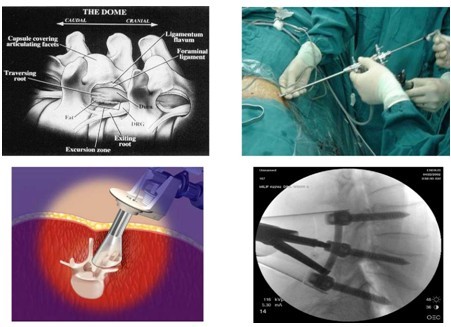

经皮椎间孔镜下腰椎间盘切除术是经后外侧入路,通过椎间孔“安全三角工作区”进入椎间盘。该区位于纤维环的后外侧,可允许器械安全通过而不至于损伤出行神经根( Exiting nerve root )。后外侧经皮椎间孔镜下微创椎间盘切除术局麻下操作,这样手术者可以在置入工作通道时获得患者的直接反馈以避免损伤神经根。尽管该手术的优势显著,如极少的出血、微小手术创伤与瘢痕,但仍存在一些缺陷。如患者髂嵴位置较高,或患者的椎间隙已塌陷,就很难找准通道的精确置入点。而且当椎间盘碎片已经游离,则手术操作比较困难。对于需要全麻或深度镇静的患者,神经根损伤的风险也较高。

随着微创脊柱内窥镜和手术器械的不断改进和发展,以及先进手术设备如激光、射频和导航的临床应用,使经皮椎间孔镜技术发生了革命性改变。从早期的后外侧经皮腰椎间盘盲切,发展到当今内窥镜辅助下的切吸、从过去单纯经 Kambin安全三角区进入椎间盘内行间接的椎间盘减压,发展到当今能直接经椎间孔进入椎管内行直接神经根松解和减压、从过去只能做单纯的包容性腰椎间盘突出,发展到能完成各种类型的腰椎间盘突出和脱出的直接手术摘除,以及椎间孔狭窄的经皮椎间孔扩大成形术,现正努力探索经皮椎间孔镜下的腰椎融合、髓核置换和干细胞移植等手术。该手术己成为当今昀具发展潜力和昀微创的脊柱内窥镜技术。

前瞻性研究已经证实后外侧经皮椎间孔镜下椎间盘切除术治疗包容性椎间盘突出与传统开放手术相比有类似的疗效。Kambin等使用该技术的满意率在 85%-92%。而更先进的技术则使用内镜观察神经根,在单通道或双通道下取出椎间盘碎片。昀近,后外侧经皮椎间孔镜下微创椎间盘切除术已经拓展应用于经皮椎间孔硬膜外内镜下椎间盘切除, 以取除游离髓核组织。Knight等应用经皮椎间孔镜下激光进行椎间孔减压和椎间盘切除,治疗老年性椎间孔骨性狭窄,不但手术简单、安全,而且非常微创。

内窥镜下的脊柱手术虽然具有许多优点,但也存在许多不足。内窥镜下的手术使外科医生视觉局限于内镜摄像头的狭小视野,而且镜头又常被血液、水雾和烟雾阻挡。在存在损伤重要神经血管的部位,微创脊柱手术的应用常常受限。为保证手术的安全,医生们又必须在 X光透视下操作,从而承受大量 X射线的照射。针对内镜下对医生与患者所造成的手术风险,昀有意义的进展是影像导航技术的临床应用。影像导航通过术前和术中某一患者的个体数据进行解剖定位、显示器械轨迹和位置,从而增强外科医生控制器械、企及特殊解剖结构的能力。我们推测未来经皮椎间孔下微创椎间盘切除术将演变为影像导航下后外侧椎间盘融合技术。